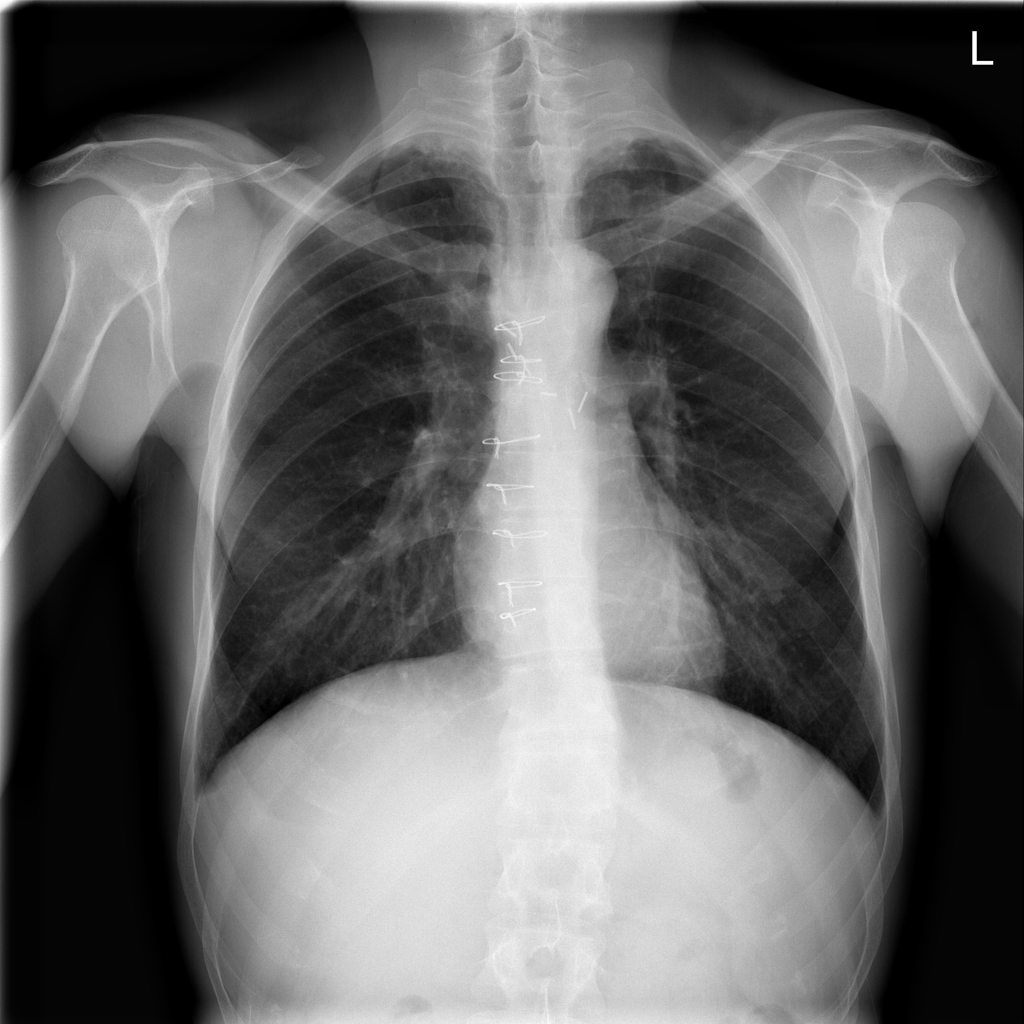

Refer to caption

Figure 3: A sample of chest x-ray (Wang et al. (2017a))

Given a medical image of a patient as input, a disease prediction system provides the probability of the occurrence of a disease. This approach represents a single-label classification problem. Examples of such diagnoses include diabetic retinopathy in eye fundus images, skin cancer in skin lesion images, and pneumonia in chest X-rays (Figure 3, Figure 3, and Figure 3). However, in certain cases, multi-label prediction becomes crucial as it provides the probabilities of multiple pathologies occurring within the same medical image. This is particularly important when there are possibilities of more than one disease being present.